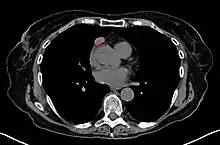

CT scan of the chest revealing a large necrotic mass in the left anterior mediastinum (indicated by the red line). Histology later established the diagnosis of a thymoma.

Another axial slice of a CT scan of the chest showing a small thymoma anterior to the heart (marked with the red line).

When a thymoma is suspected, a CT/CAT scan is generally performed to estimate the size and extent of the tumor, and the lesion is sampled with a CT-guided needle biopsy. Increased vascular enhancement on CT scans can be indicative of malignancy, as can be pleural deposits.[1] Limited biopsies are associated with a very small risk of pneumomediastinum or mediastinitis and an even-lower risk of damaging the heart or large blood vessels. Sometimes thymoma metastasize for instance to the abdomen.[5]